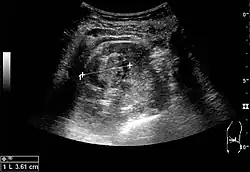

The hydronephrosis is typically graded visually and can be divided into five categories going from a slight expansion of the renal pelvis to end-stage hydronephrosis with cortical thinning (Figure 15). The evaluation of hydronephrosis can also include measures of calyces at the level of the neck in the longitudinal scan plane, of the dilated renal pelvis in the transverse scan plane and the cortical thickness, as explained previously (Figure 16 and Figure 17).[1]

Figure 16. Hydronephrosis with dilated anechoic pelvis and calyces, along with cortical atrophy. The width of a calyx is measured on the US image in the longitudinal scan plane, and illustrated by '+' and a dashed line.[1]

Figure 17. Same patient as in Figure 16 with measurement of the pelvis dilation in the transverse scan plane illustrated on the US image with '+' and a dashed line.[1]